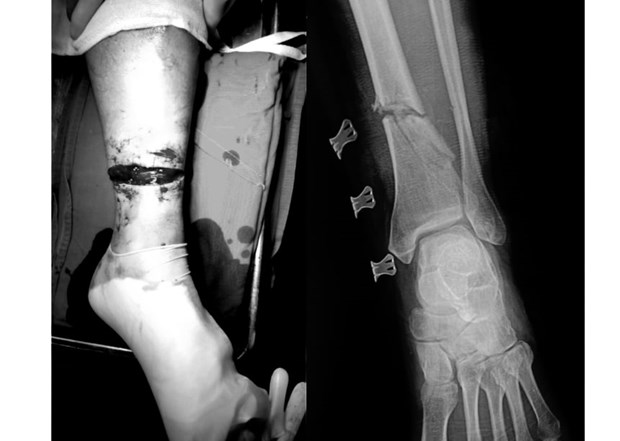

Một người đàn ông ở Hòa Binh đã bị lưỡi máy cắt cỏ văng trúng chân trong lúc làm việc. Được người thân đưa vào viện với tình trạng vết thương rất nặng. Dưới đây là những thông tin cụ thể. Khi ông L. đang cắt cỏ, lưỡi cưa không may vấp vào viên đá, vỡ và cắt vào chân do máy cắt cỏ đã bị tháo tấm sắt chắn lưỡi cưa.

Ngày 31/12/2019, Bệnh viện Hữu nghị Việt Đức tiếp nhận trường hợp một người đàn ông bị tai nạn khi cắt cỏ, khiến lưỡi cưa cắt đứt chân.

Bệnh nhân tên B.V.L (56 tuổi, ở Hòa Bình) nhập viện trong tình trạng vết thương hở đứt 3/4 chu vi cẳng chân trái, chảy nhiều máu. Bệnh nhân bị mất vận động cổ chân và các ngón chân, gãy hở xương, đứt hoàn toàn các gân cơ khu trước và sau cẳng chân, đứt bó mạch chày sau, chày trước.

Người nhà của bệnh nhân cho hay, khi ông L. đang cắt cỏ, lưỡi cưa không may vấp vào viên đá, vỡ và cắt vào chân do máy cắt cỏ đã bị tháo tấm sắt chắn lưỡi cưa.

Sau khi xảy ra tai nạn, ông L. đã được sơ cứu băng ép tại bệnh viện huyện, sau đó chuyển Bệnh viện Hữu nghị Việt Đức vào ngày 31/12/2019.

Bác sỹ Hoàng Minh Thắng - Khoa Phẫu thuật Chi trên và Y học thể thao cho biết, người bệnh đã được cố định ngoài xương chày, nối gân, thần kinh, nối động mạch chày trước, chày sau.

Hiện tại sau mổ, tình trạng bệnh nhân đã ổn định, đầu chi hồng ấm, mạch chày trước, chày sau rõ và đang được hướng dẫn tập phục hồi chức năng.

Bác sỹ Thắng khuyến cáo, người dân cần có ý thức đảm bảo an toàn lao động, kiểm tra dụng cụ kỹ lưỡng trước khi sử dụng nhằm tránh những tai nạn đáng tiếc./.